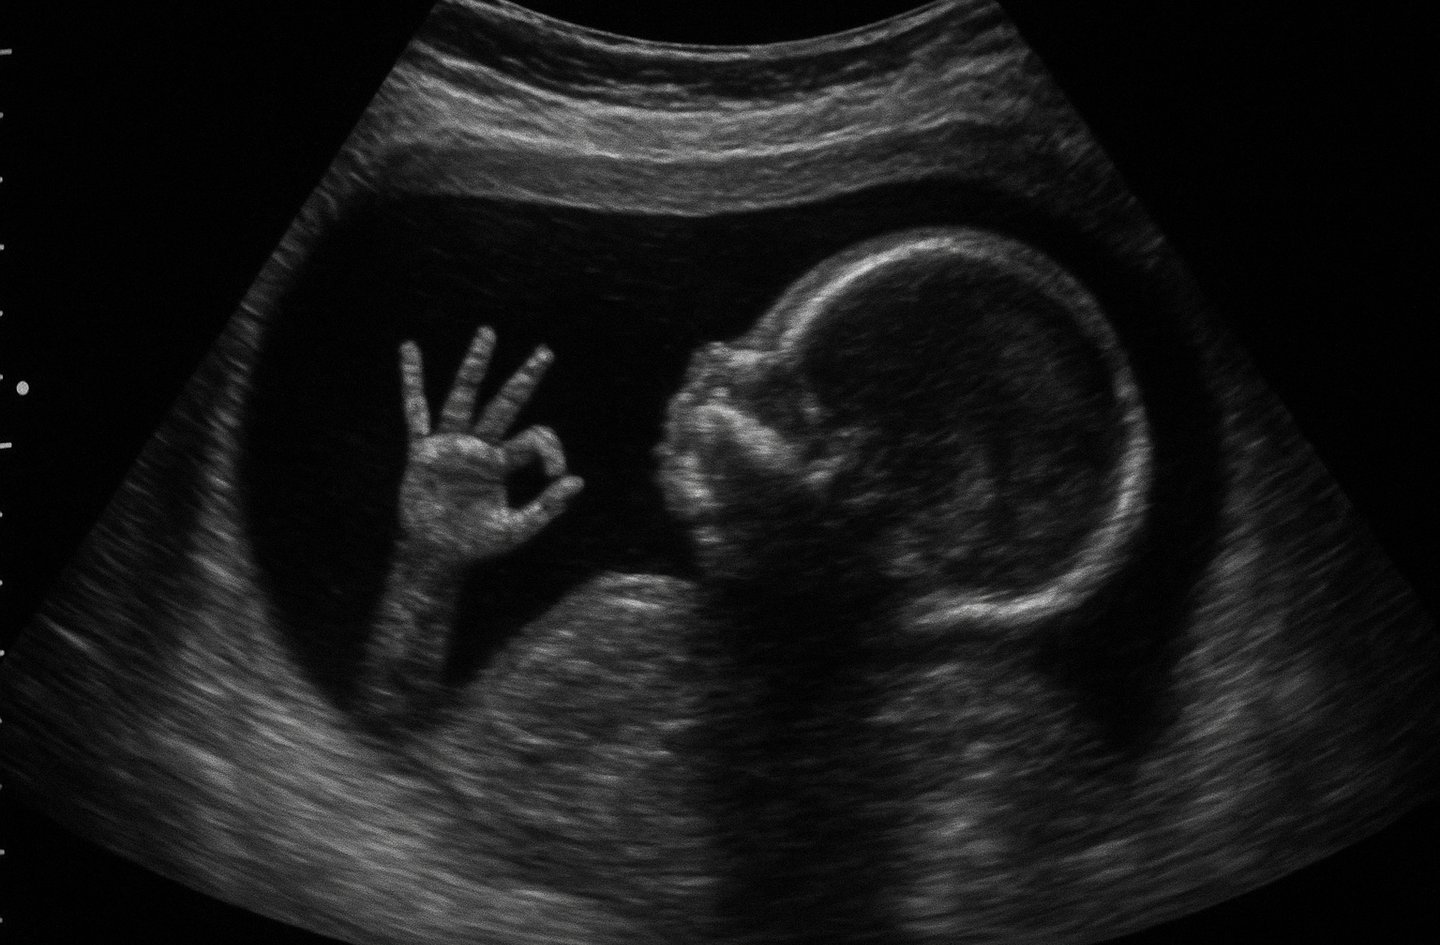

Le Spina Bifida est une malformation du tube neural, structure embryonnaire qui donnera naissance à la moelle épinière.

Elle se traduit par une fermeture incomplète de la colonne vertébrale, provoquant des troubles moteurs, urinaires et neurologiques variables selon la gravité de la lésion.